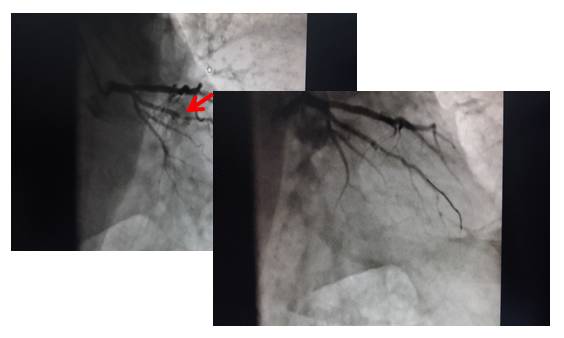

冠脉造影及PCI(2015-10-16)